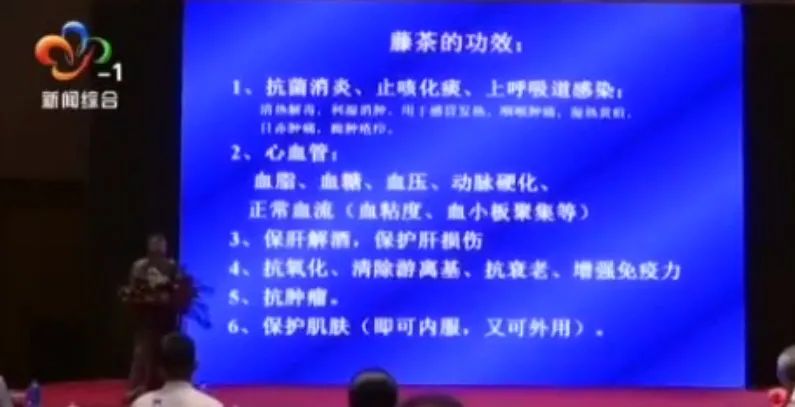

02 | 张家界土家莓茶九大功效作用 |